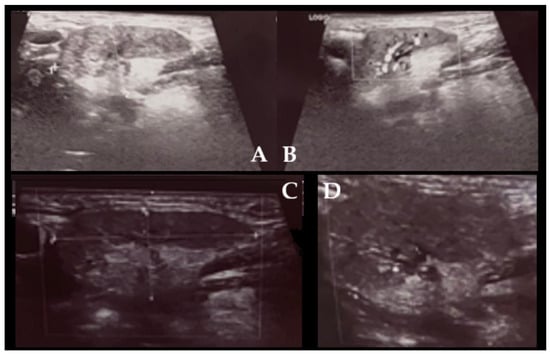

It is with great pleasure that I invite you to submit articles for the “Interesting images” Special Collection. Since we introduced Interesting Images as an article type in Diagnostics, it has served as a valuable resource for the imaging community. Many have relayed that they use these image-based case reports when encountering challenging cases or images of diseases rarely seen. Further, pitfalls are covered by this type of article and may be helpful both for experienced and less experienced image readers in making a correct evaluation.

The interesting Images together serve as a live imaging atlas covering PET, CT, MRI, and other imaging modalities. Therefore, the more cases we publish, the more likely it is that image interpreters with a difficult case can be supported by previously published cases. Although focus until now has largely been on clinical cases, it should be noted that nonclinical cases are also welcome, e.g., from preclinical in vivo imaging, including optical imaging as well as histology images from pathology.